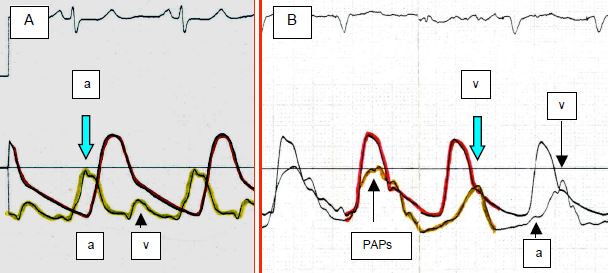

- 6.5.6 Pressions enregistrées